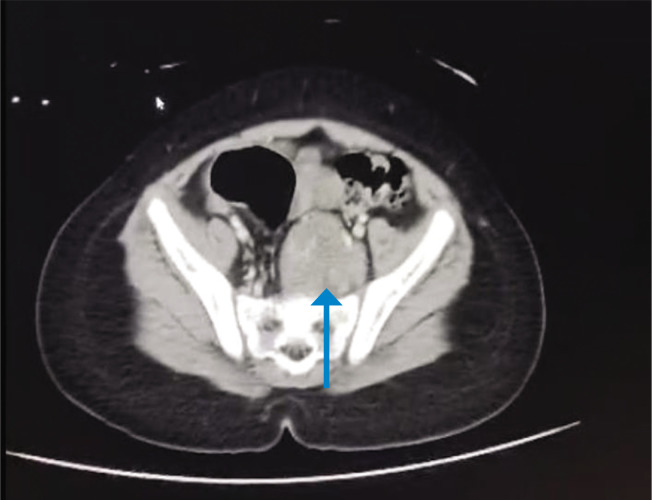

速发性肥胖伴下丘脑功能障碍、通气不足、自主神经失调和神经嵴肿瘤(ROHHAD-NET)虽然是一种罕见的疾病,但具有潜在的致命性。了解和紧急诊断是至关重要的。我们在此报道三起连续案件,这是印度首次发生此类案件。18个月以上的儿童通常以体重快速增长为主要症状。下丘脑功能障碍可能导致内分泌问题、呼吸功能障碍和自主神经失调。多年来,随着时间的变化,出现一种或多种下丘脑功能障碍的迹象:高泌乳素血症、生长激素缺乏症、中枢性甲状腺功能减退症、中枢性肾上腺功能不全或库欣综合征、青春期提前或延迟、水电解质平衡紊乱。诊断是困难的,因为没有可靠的测试,治疗主要是支持性的。这三个发育良好的孩子都表现出体重迅速增加,然后出现了下丘脑功能障碍的症状。其中一个偶然发现神经嵴肿瘤,第二个有持续性高钠血症,第三个孩子表现为肠梗阻。各种各样的表现和模糊的症状谱对临床医生的诊断提出了挑战,并强调了创造意识的重要性。由于临床上很难将ROHHAD综合征与其他遗传来源的肥胖综合征区分开来,因此需要个性化的策略方法。

Rapid-onset obesity with hypothalamic dysfunction, hypoventilation, autonomic dysregulation and neural crest tumor (ROHHAD-NET) though a rare disease, is potentially fatal. It is of utmost importance to be understood and urgently diagnosed. We hereby report a series of three cases, the first of its kind from India. Children older than 18 months old usually exhibit rapid weight growth as a presenting symptom. Hypothalamic dysfunction could lead to endocrine issues, respiratory dysfunction and autonomic dysregulation. Over the years, with variable timing, one or more signs of hypothalamic dysfunction appear: hyperprolactinemia, growth hormone deficiency, central hypothyroidism, central adrenal insufficiency or Cushing syndrome, early or delayed puberty, water-electrolyte balance disorders. The diagnosis is difficult because there is no reliable test, and the treatment is mainly supportive. All the three children who were thriving well, presented with rapid weight gain and then developed symptoms of hypothalamic dysfunction. While in one a neural crest tumor was incidentally detected, the second had persistent hypernatremia and the third child presented with intestinal obstruction. The varied presentation and vague symptom spectrum exhibit a diagnostic challenge to the clinician and underscores the importance of creating awareness. An individualized strategic approach is needed as it is clinically difficult to distinguish ROHHAD syndrome from other obesity syndromes of genetic origin.